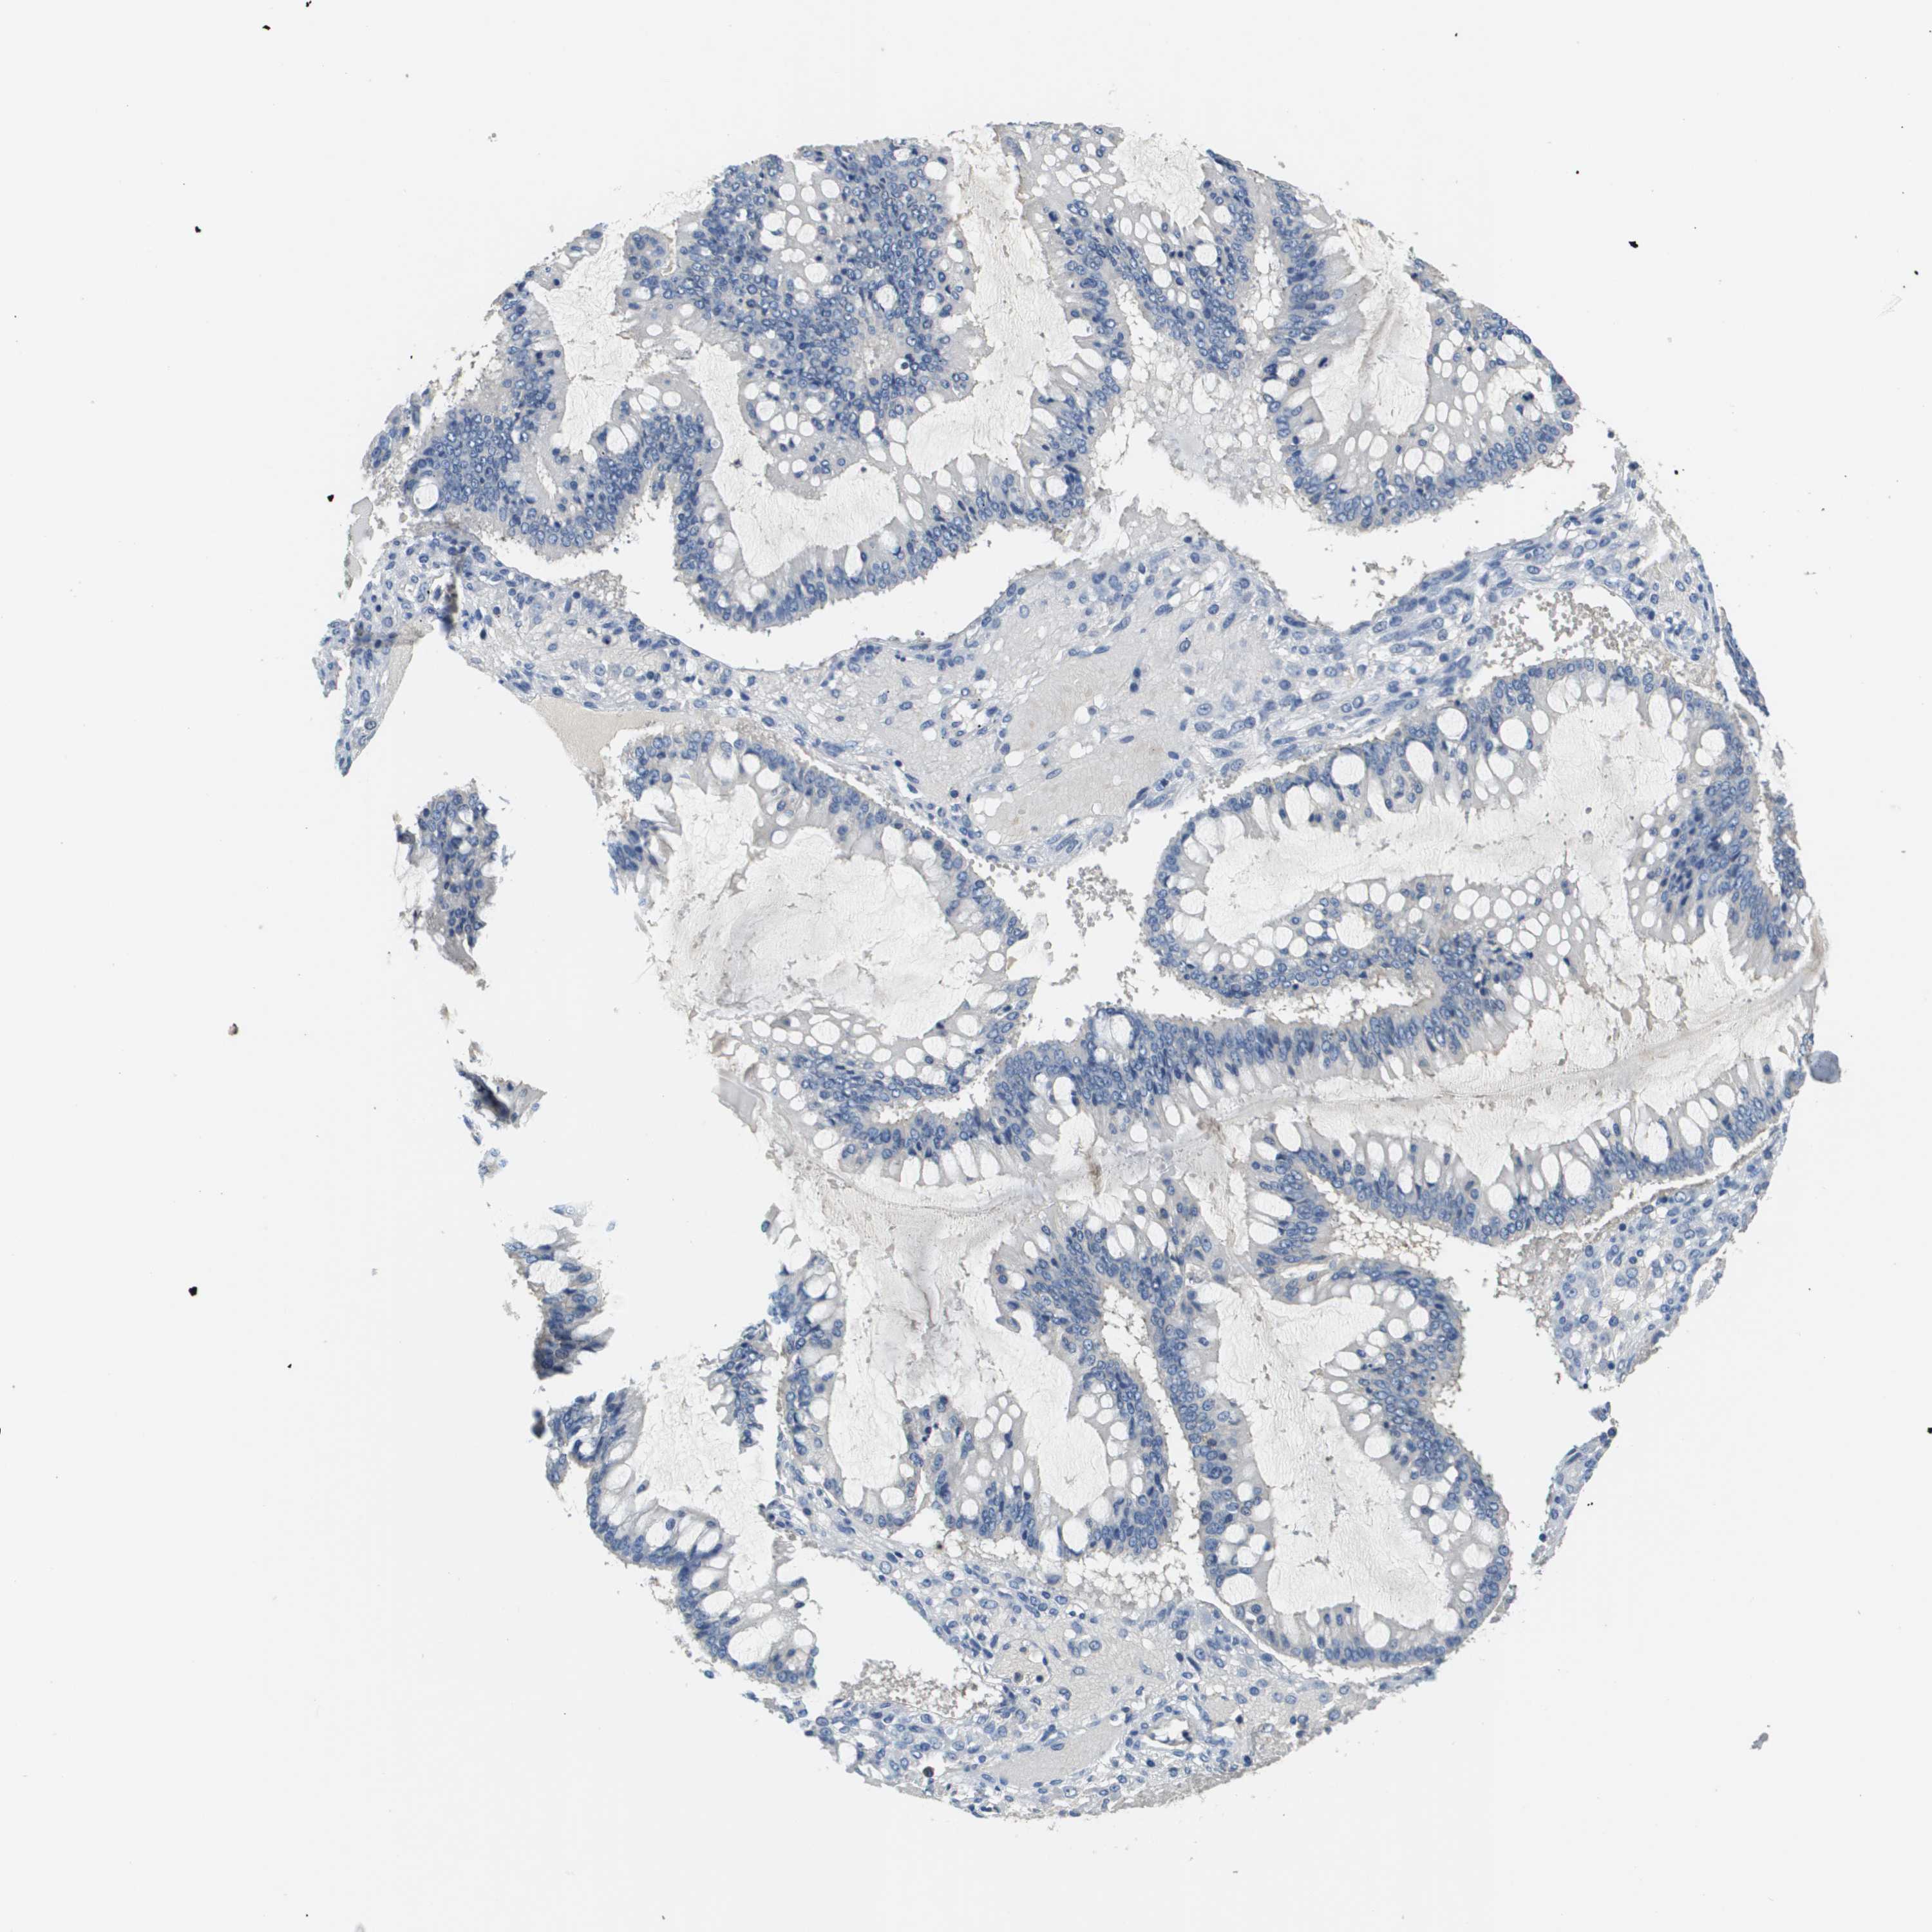

OVARIAN CANCER - Protein expressioni

A mouse-over function shows sample information and annotation data. Click on an image to view it in a full screen mode. Samples can be filtered based on level of antibody staining by selecting one or several of the following categories: high, medium, low and not detected. The assay and annotation is described here.

Note that samples used for immunohistochemistry by the Human Protein Atlas do not correspond to samples in the TCGA dataset.

Antibody stainingi

Antibody staining in the annotated cell types in the current human tissue is reported as not detected, low, medium, or high, based on conventional immunohistochemistry profiling in selected tissues. This score is based on the combination of the staining intensity and fraction of stained cells.

Each image is clickable and will lead to virtual microscopy that enables deeper exploration of all samples and also displays staining intensity scores, fraction scores and subcellular localization as well as patient and tissue information for each sample.

Antibody HPA021451

Antibody CAB017490

Cystadenocarcinoma, serous, NOS

Carcinoma, endometroid

Cystadenocarcinoma, mucinous, NOS

Carcinoma, NOS